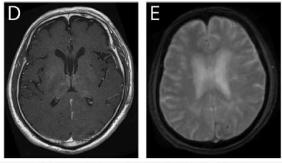

复查脑脊液行14-3-3蛋白和其他病原学检查(包括日本脑炎病毒、革等热病毒、基孔肯雅病毒)。因神经功能缺损加重,复查神经影像示直径8mm的左侧枕叶实质出血。

尽管栓塞治疗后血流减少,但患者的MRI表现仍在进展。在没有进一步介入或手术选择的情况下,持续进展风险大于抗凝治疗风险。

因此,患者接受了抗凝治疗。其他高凝状态检查包括蛋白C/蛋白S、V因子Leiden突变、凝血酶原20210A、抗心磷脂抗体及β2糖蛋白均阴性。抗凝治疗1周后神经影像未见继续进展。患者意识水平、言语功能及随意运动改善,并好转出院。